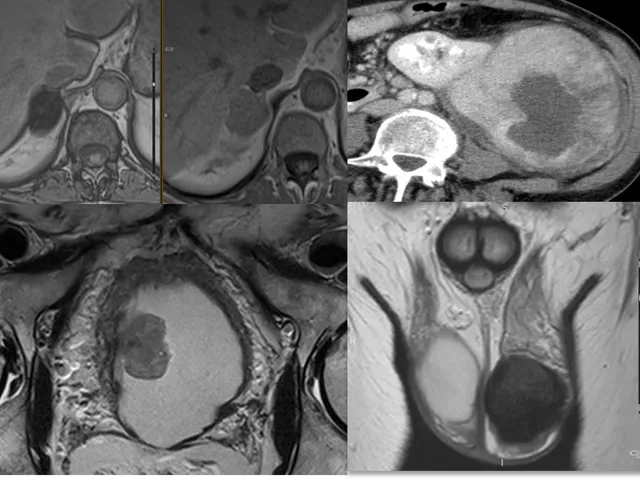

This remote fellowship includes an overview of the most common retroperitoneal and urologic pelvic diseases (excluding prostate) with the main objective to become more confident in reading retroperitoneal and urologic pelvic CT and MR studies.

Lectures on relevant anatomy, MR and CT protocols, characterization of adrenal, retroperitoneal, excretory tract, bladder and scrotal masses, VIRADS classification for bladder cancer, tumour staging and follow-up will be presented.

• Lectures on reading CT/MRI for characterisation of adrenal and retroperitoneal masses, the excretory tract, urinary bladder and scrotum, VIRADS classification and urinary tract / bladder cancer staging and follow-up